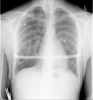

Anbei zwei Bilder vor der TB-OP im Jahr 2010

Das erste Bild entstand nach der TB-OP im Jahr 2010 im Klinikum Berlin-Buch.

Das zweite Bild entstand ca. 1 1/2 Jahre nach der OP.

Bilder nach und unmittelbar vor der Bügelentnahme folgen in kürze.

Anbei noch ein Bild während der Zeit mit Bügel

Vielleicht kann man es auf dem Bild etwas besser erkennen was ich im vorherigen Post mit "Millimeterbereich" meinte.

Wie gesagt, es geht hier nur um den Ansatz. Mit dem Ergebnis der OP bin/war ich zufrieden.